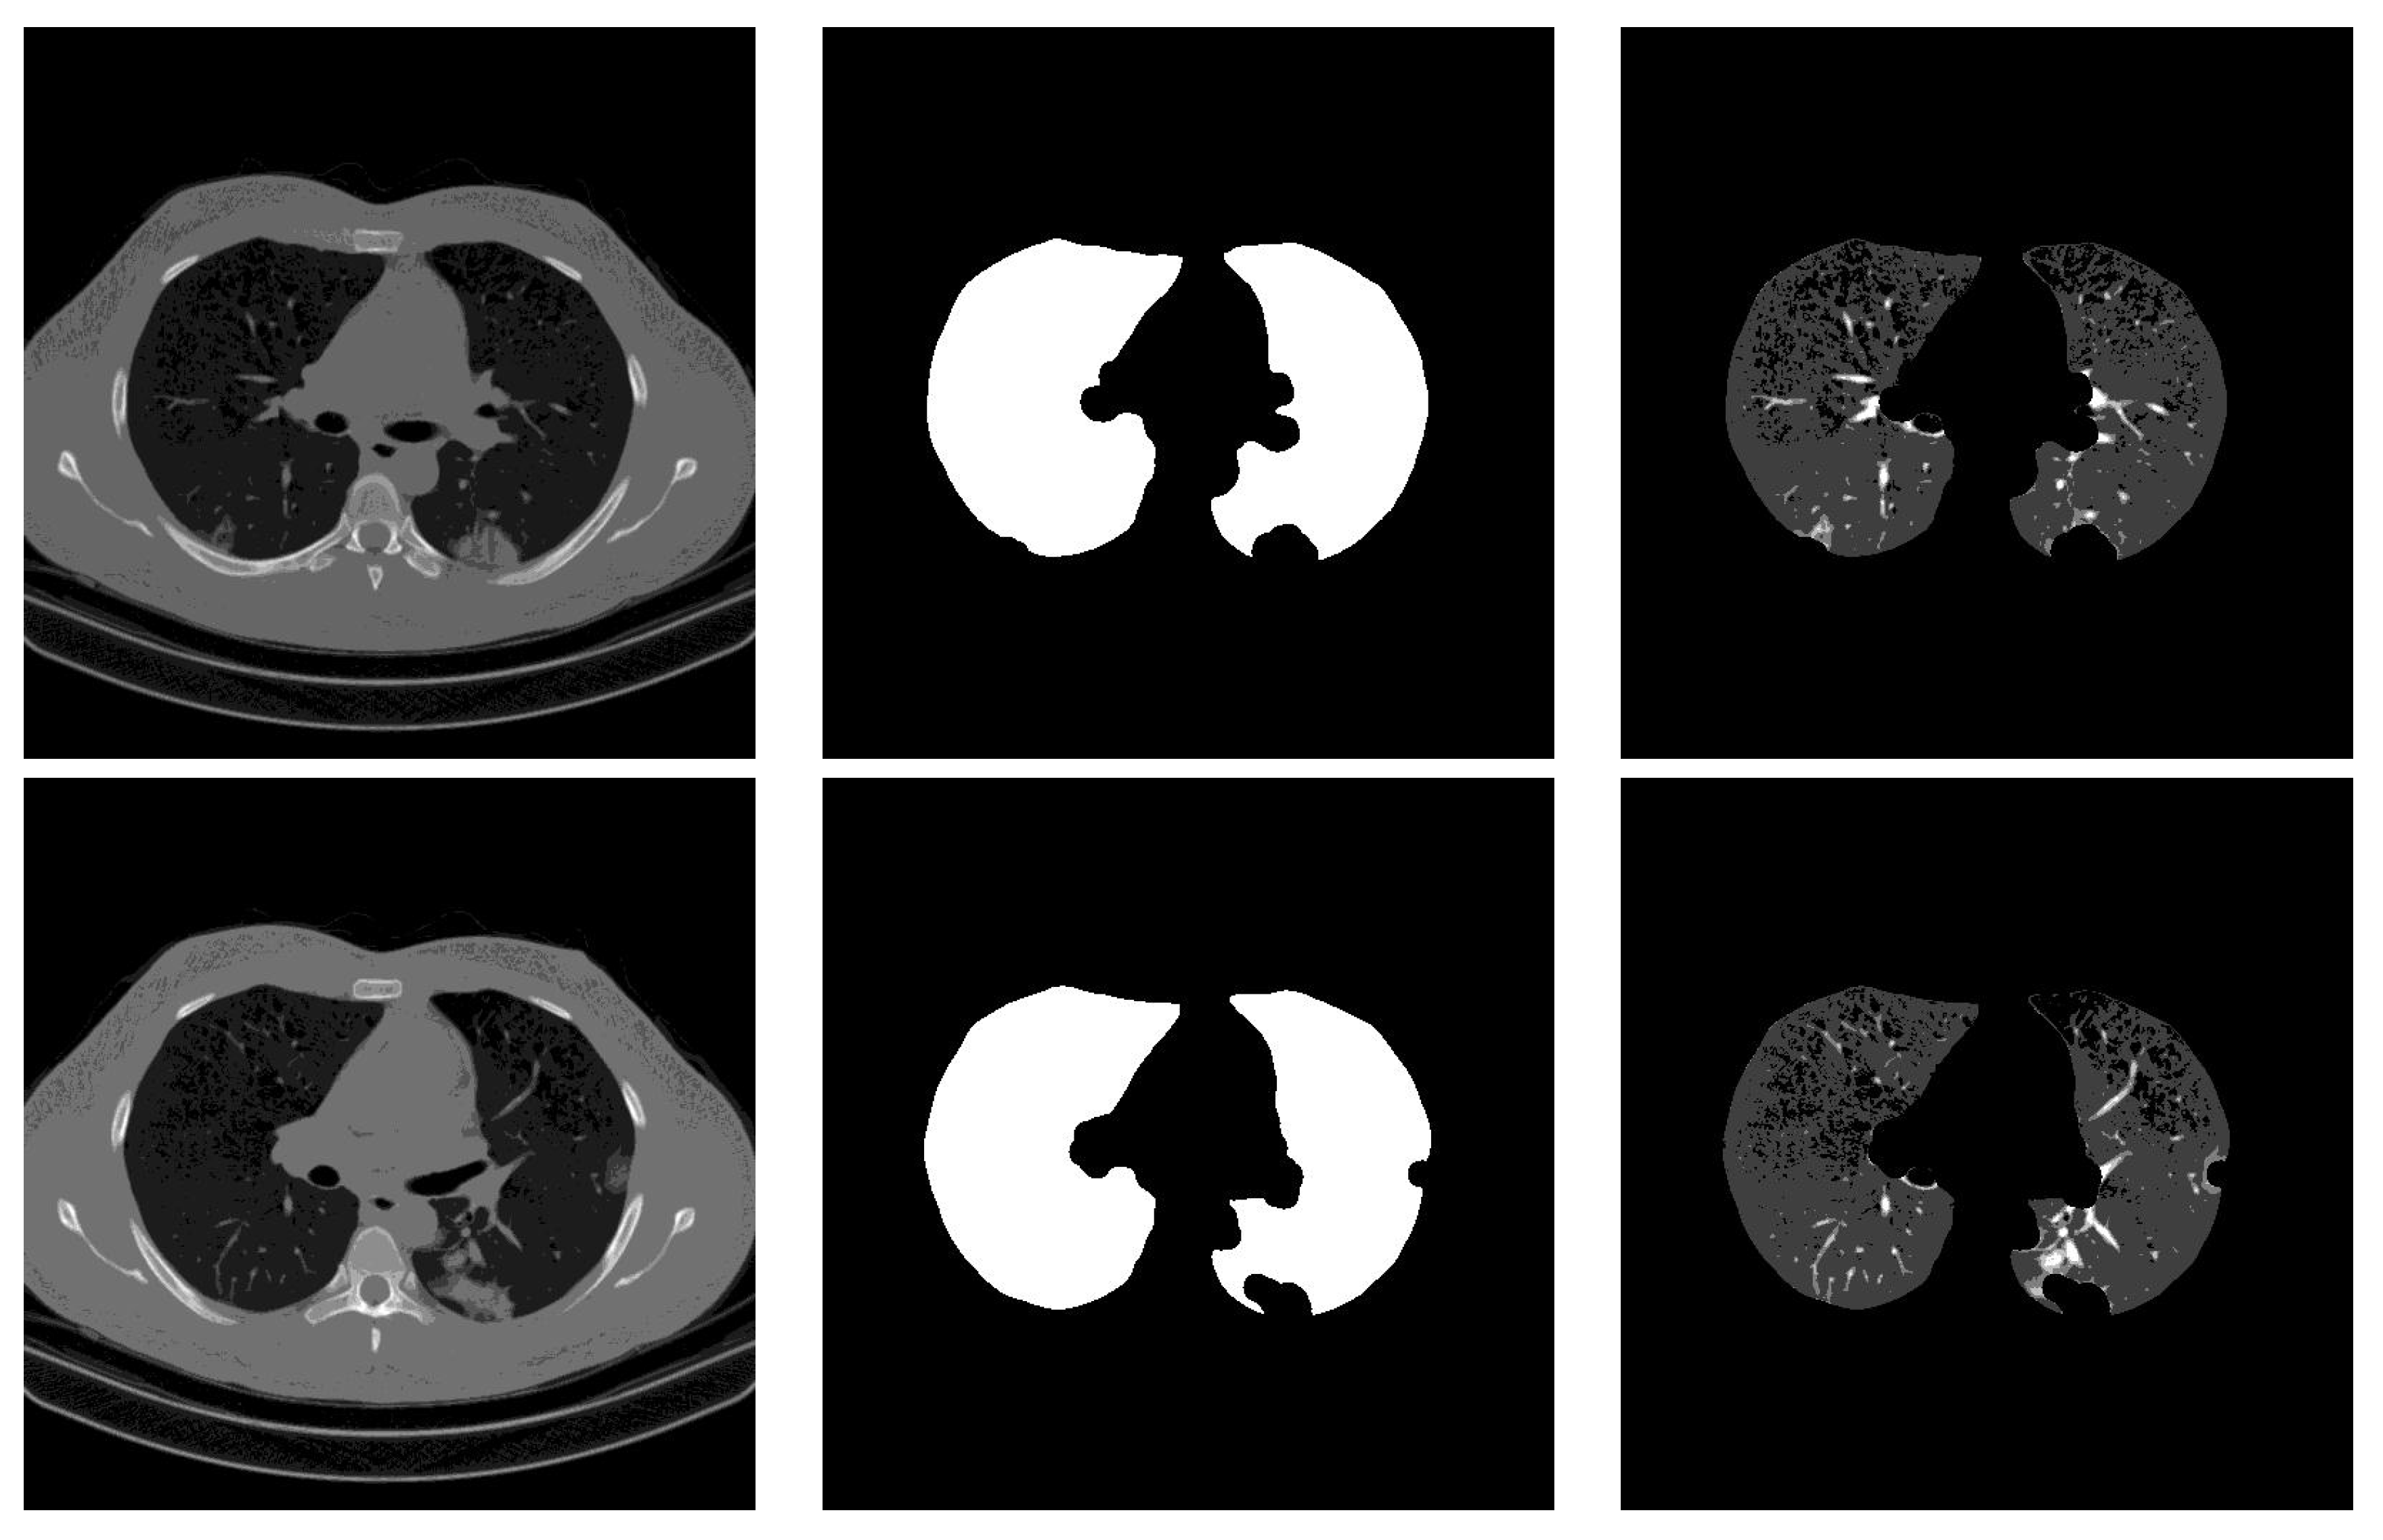

In the preprocessing phase, we read the slice images from the “.dcm” file format which gives one channel image (grayscale), where we did not use any contrast-enhancement technique. Since most CNN architectures were designed for color images, we propose stacking the gray image, the segmented lung lobes image, using the proposed method in [28] and the multiplication of the grayscale image with the binary lung lobes mask. Figure 3 shows an example of the original image, the segmentation result, and the result of stacking the three channels. In addition to having three channels as input to the CNN architectures, the segmentation guides the slices’ classification by concentrating on the lung lobes’ features and removing non-relevant ones.

Figure 3.

Preprocessing phase.

4.2.2. Stacking Grayscale Image with the Segmented Result

In this experiment, we proposed segmenting the lung lobes and then stacking the segmentation result with the raw slice image to obtain an RGB-like image as illustrated in Figure 3. Similar to the stacking grayscale experiment, all CNN models were fine-tuned for 20 epochs with the Adam optimizer [36]. The initial learning rate is 0.0001, which decays by 0.1 after 10 epochs, followed by another decay of 0.1 after 15 epochs. Table 2 summarizes the obtained results of the four CNN architectures. From these results, we notice that the Densenet-161 architecture achieved a slightly better result than the other three CNN architectures. In general, the four CNN architectures achieved close results.

Figure 7 contains the confusion matrices of the trained CNN architectures (ResneXt-50, Densenet-161, Inception-v3, and Wide-Resnet-50) on the validation data. From these confusion matrices, we notice that the Wide-Resnet-50 architecture achieved the best performance on the recognition of normal and COVID-19 slices with accuracies of 94.78% and 84.47%, respectively. On the other hand, for Cap slices recognition, the Densenet-161 architecture achieved the best performance with an accuracy of 58.03%.

By comparing the results of Table 1 and Table 2, we notice that stacking the segmentation of lung lobes considerably improved the results of all four CNN architectures. Similarly, when we compare the confusion matrices of Figure 6 and Figure 7, we notice that the best recognition rate of all three classes improved, especially for the COVID-19 rate, which improved by 18.6%. This proves the importance of stacking the segmented lung lobes with the grayscale image in our approach.